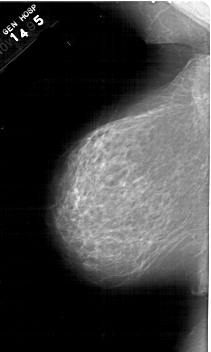

A_1467_1.LEFT_MLO

LEFT_MLO LINES 6331 PIXELS_PER_LINE 3781 BITS_PER_PIXEL 12 RESOLUTION 43.5 NON_OVERLAY